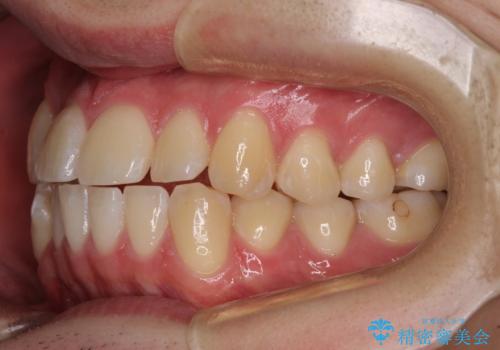

八重歯と前歯のクロスバイト ワイヤー装置で短期間矯正

上顎側切歯(前から2番目の歯)が内側に転位している歯列は、インビザラインでは排列が困難であることが多いため、期間を短く、より良い仕上がりとするため、ワイヤー装置にて矯正治療を行うこととしました。

治療開始の頃は、食事や歯磨きが慣れず、装置が頻繁に脱落しましたが、2,3ヶ月ほどで慣れ、その後は1年ほどで治療を終えることができました。